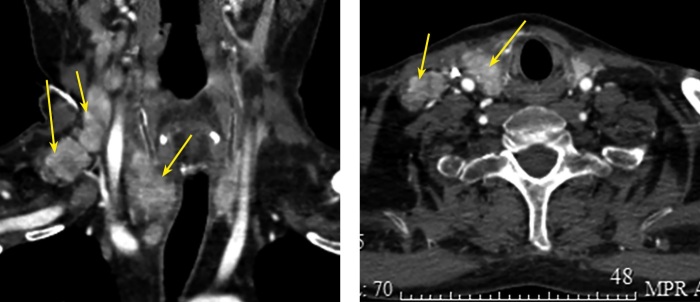

Medullary thyroid carcinoma is a rare aggressive tumor of thyroid gland. Due to its neuroendocrine origine medullary thyroid carcinoma can be the source of ectopic production of different peptides and hormones. We describe a unique case of severe ACTH-dependent Cushing's syndrome due to ectopic corticotropin production by medullary thyroid carcinoma in a male patient of 39 years old with calcitonin level more than 4000 pg/ml (<11,8), thyroid nodule, multiple neck jugular and central lymphnodes. The potassium level was 1,34 mmol/l (3,5-5,1), hypercortisolemia up to 1613,2 nmol/l (185-624) with elevated level of ACTH up to 24,7 pmol/l (1,03-10,74). After the correction of water and electrolytes disorders an operation was performed - thyroidectomy, central and lateral neck dissection. Postoperative calcitonin decreased to 126 pg/ml (<11,8), calcium and parathormone blood levels remained normal. The potassium level didn't decrease without any pharmacological treatment. There was a sharp fall in postoperative blood levels of cortisol and ACTH. The hormonal replacement treatment with hydrocortisone was induced. Morphological examination showed medullary carcinoma with ACTH production in tumor nodule, with metastatic neck lymph nodes. Thus this is a rare case and successful treatment of patient with severe hypercortisolism by thyroidectomy and neck lymphnodes dissection.